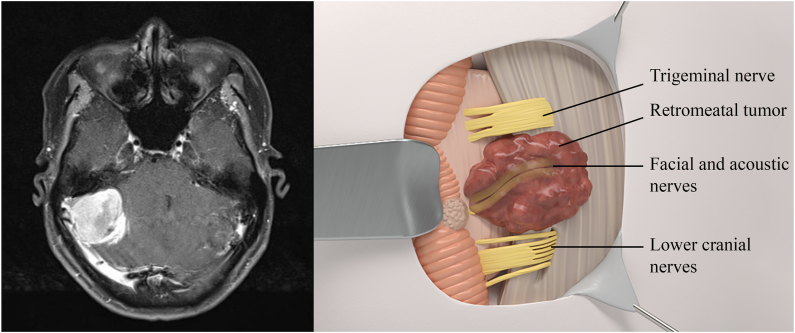

Fig. 1.

Left: MRI scan of retrometal meningioma. Right: Relationship of cranial nerves to retrometal meningioma using 3D illustration.

Retromeatal meningiomas (Fig. 1) are relatively safer to resection than other groups of CPA meningiomas thanks to the tumor being superficial, involving mostly the cerebellum. Cranial nerves are pushed anteriorly and inferiorly. More specifically, the VII/VIII complexes are pushed anteriorly (85 %) or inferiorly (15 %). The lower cranial nerves IX, X, XI, and PICA are pushed inferiorly. In addition, the site of dural attachment is between the IAM and the sigmoid sinus. As a result, devascularization and debulking were more favorable.